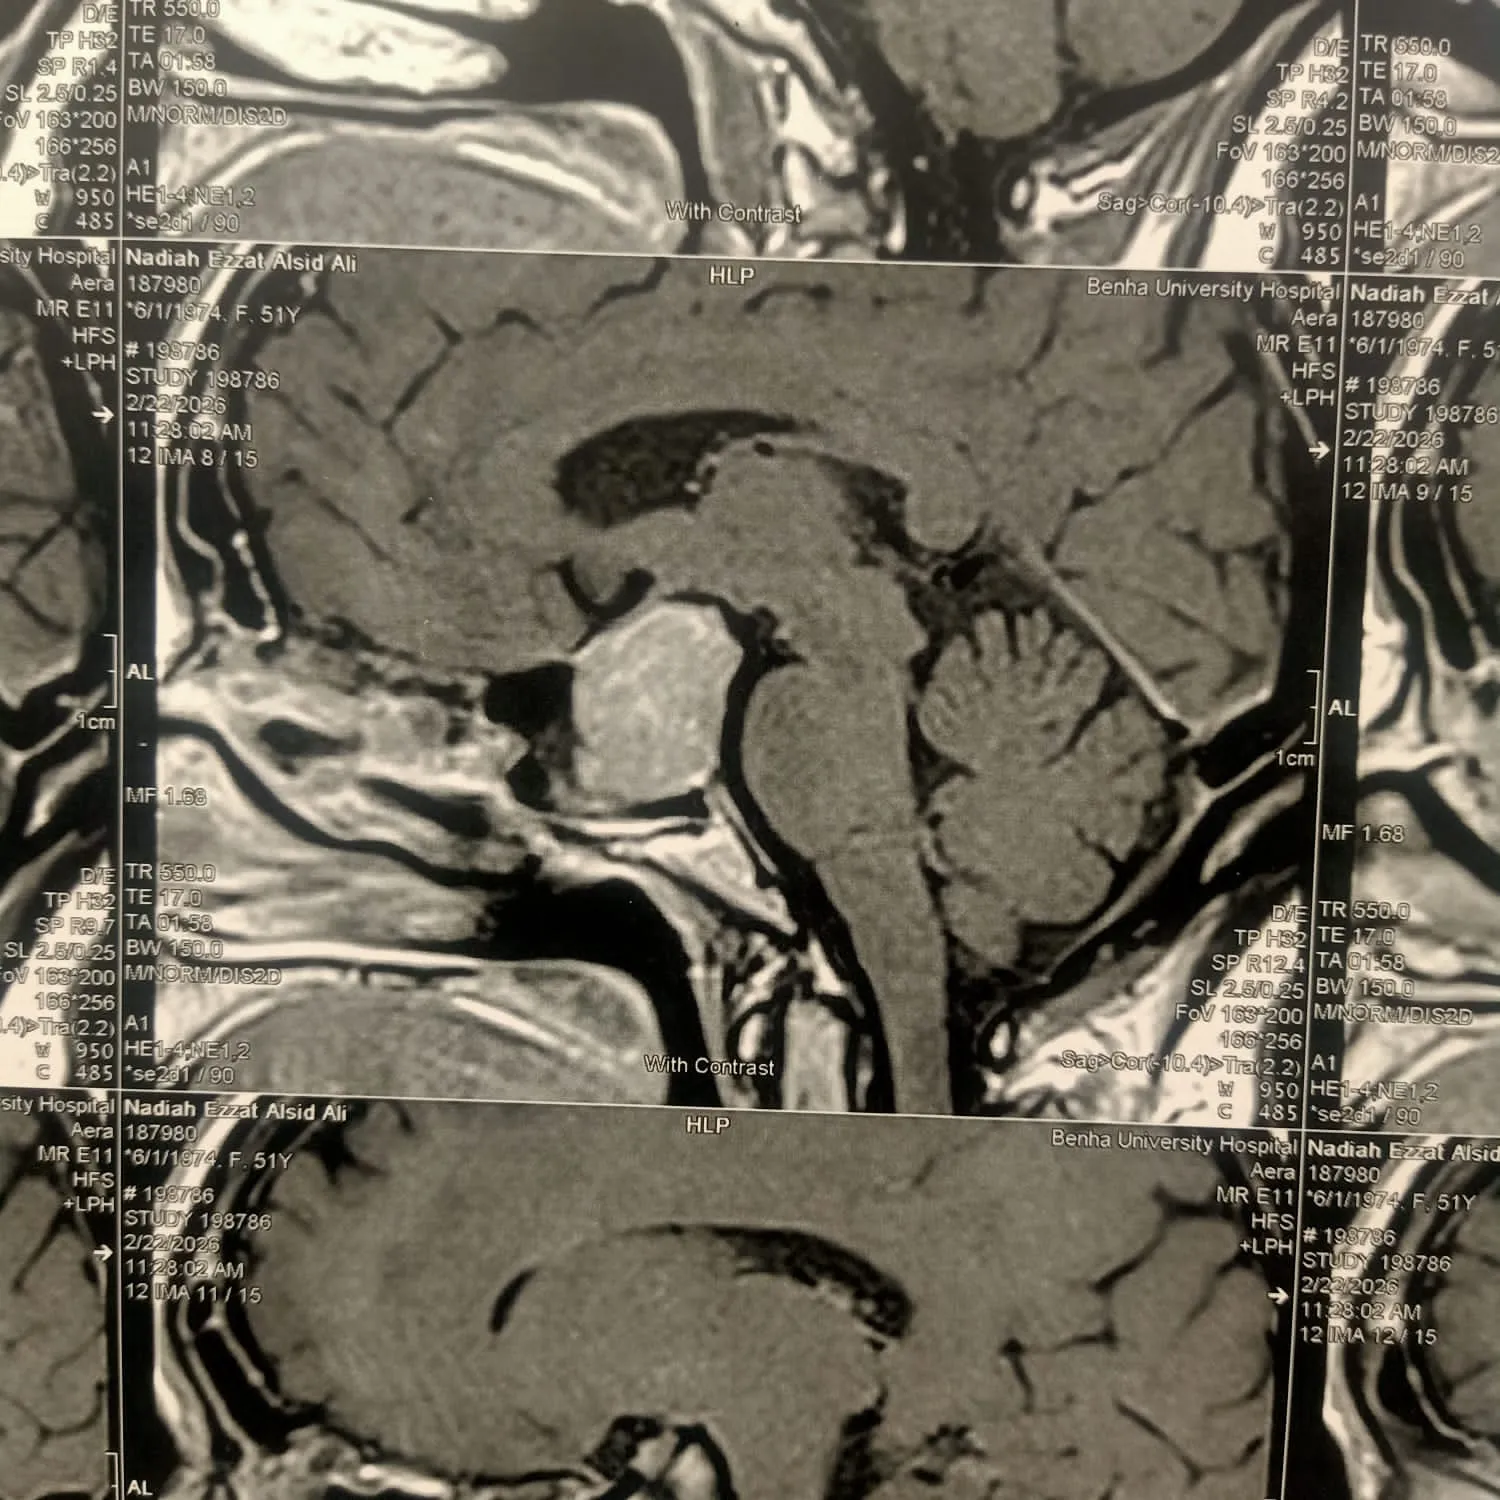

وكانت المريضة تعاني من ضعف شديد في الإبصار، وصداع مستمر، إلى جانب اضطرابات هرمونية، حيث كشفت الفحوصات الطبية عن وجود ورم بالغدة النخامية يضغط بشكل مباشر على العصب البصري.

وتمكن الفريق الطبي من استئصال الورم بالكامل باستخدام المنظار عبر الجيوب الأنفية، في جراحة مشتركة بين قسمي جراحة المخ والأعصاب والأنف والأذن والحنجرة، دون إجراء أي فتح جراحي خارجي للجمجمة.

وأكدت إدارة المستشفيات أن الحالة الصحية للمريضة مستقرة تمامًا وبوعي كامل، وتخضع حاليًا للمتابعة الطبية الدقيقة بعد التأكد من الاستئصال الكامل للورم من خلال الأشعة المقطعية، تمهيدًا لخروجها من المستشفى خلال الفترة المقبلة.